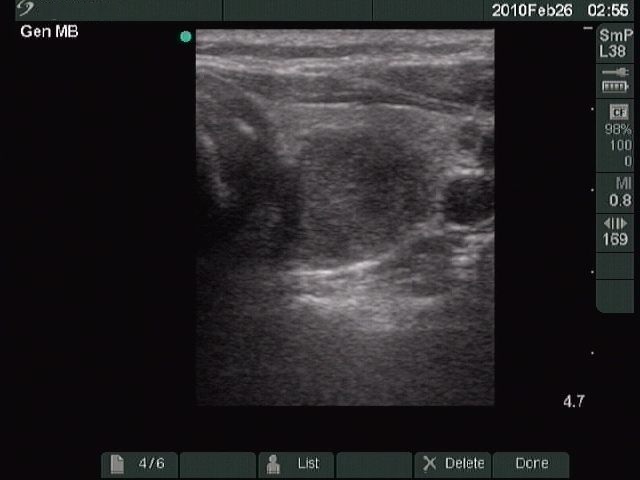

Benign nodular hyperplasia - Case 27. |

Clinical presentation: a 48-year-old woman was referred for an evaluation of a 'lump in the throat' feeling.

Palpation: both lobes of the thyroid were enlarged, but caused no complaints to the patient.

Functional state: euthyroidism.

Ultrasonography: multinodular goiter.

Cytological report: benign colloid goiter.

Suggestion: follow-up examination.